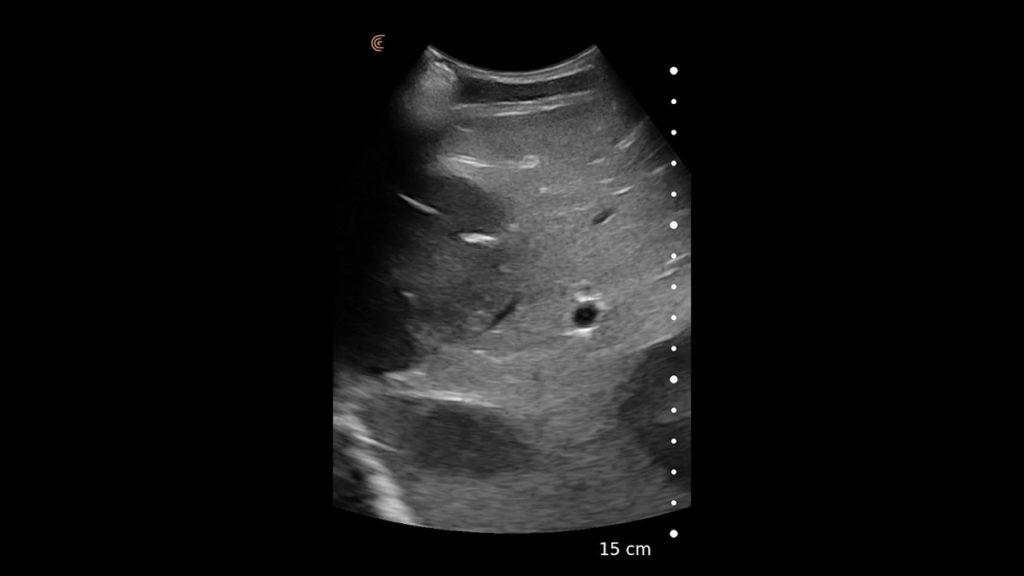

Using the jejunum as an important landmark, the hypoechoic jejunal lymph nodes can be identified. In this video Dr. Edwards explains the ultrasound appearance of normal jejunal nodes.